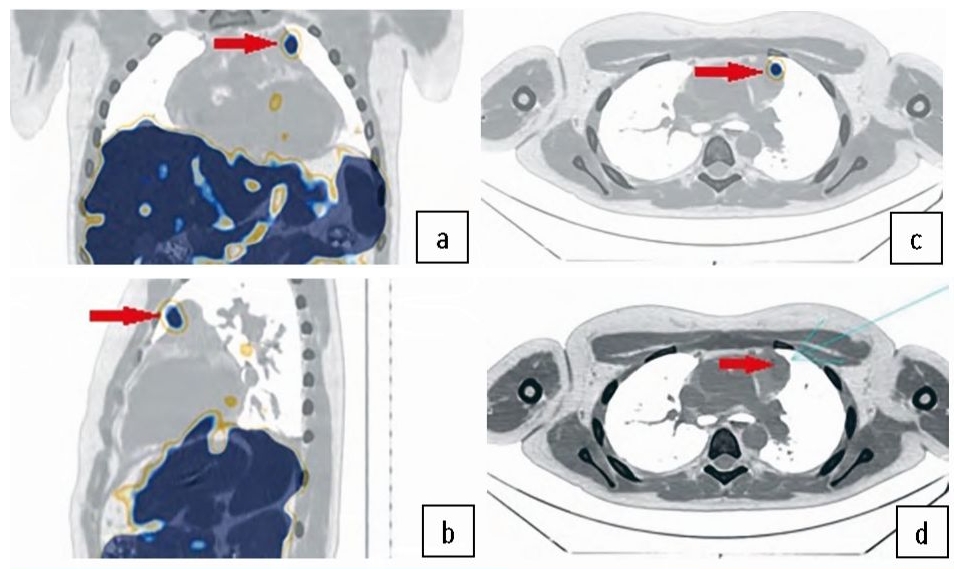

Описание клинического случая

Пациент В., 13 лет. В октябре 2017 г. появились жалобы на многократную рвоту, интенсивные головные боли. Далее отмечалась постепенная прибавка в весе, перераспределение подкожной жировой клетчатки по кушингоидному типу, увеличение окружности и покраснение лица – «матронизм», повышение артериального давления до 180 и 100 мм рт. ст. Госпитализирован в отделение эндокринологии детской больницы в декабре 2017 г., где подтвержден синдром эндогенного гиперкортицизма (отрицательная малая дексаметазоновая проба: кортизол в крови утром – 1203 нмоль/л (норма – менее 50), кортизол в крови вечером – 3069 нмоль/л (норма – 64–327), АКТГ вечером – 139 пг/мл (норма – 2–25,5). Выполнена магнитно-резонансная томография головного мозга с внутривенным контрастированием: данных, свидетельствующих об образовании в гипофизе, не получено. По данным компьютерной томографии (КТ) ОГК от 10.01.2018 выявлены признаки объемного образования верхнего средостения. Учитывая клинические и лабораторные данные, заподозрена АКТГ-продуцирующая НЭО средостения. Выполнена соматостатин-рецепторная сцинтиграфия (СРС) всего тела с 111In-DTPA-octreotide (Octreoscan) от 06.02.2018 на томографе General Electric Discovery NM/CT 670. В верхнем средостении слева в проекции тимуса визуализировано округлое образование с четкими ровными контурами неоднородной плотности (35–50 HU) с наличием гиперденсивных включений (до 80 HU) размерами 25×23×23 мм, низкоинтенсивно накапливающее радиофармацевтический лекарственный препарат (РФЛП). Выше над указанным образованием парааортально визуализировано дополнительное образование – лимфатический узел(?) – размерами 12×10×11 мм, не накапливающее РФЛП (рис. 1).

Рис. 1. СРС и однофотонная эмиссионная КТ с рентгеновской компьютерной томографией с 111In-DTPA-octreotide (Octreoscan).Образование тимуса с признаками накопления РФЛП (стрелка).

Fig. 1. Somatostatin receptor scintigraphy (SRS) and single-photon emission computed tomography with X-ray computed tomography with 111In-DTPA-octreotide (Octreoscan). Thymus mass with signs of increased radiopharmaceutical uptake (arrow).